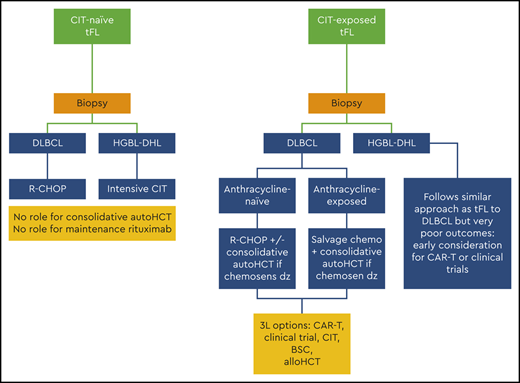

Patient 1 was a 59-year-old man who initially presented with an acute abdomen while traveling. He was found to have appendicitis but also was noted to have multiple retroperitoneal lymph nodes. An inguinal lymph node biopsy revealed follicular lymphoma (FL) grade 1 to 2. Staging showed diffuse adenopathy (largest lymph node, 4.6 cm). He had mild anemia but a normal lactate dehydrogenase (LDH) level. He was treated with bendamustine and rituximab that required dose reduction due to cytopenias for cycles 5 and 6. Twenty-two months later, he had progressive adenopathy in the axillary region. A biopsy again showed FL, but it was now grade 3A. A bone marrow biopsy was performed, which showed a hypercellular marrow (70%) comprised largely of CD20+CD10+BCL2+ large cells consistent with transformed follicular lymphoma (tFL) (Figure 1).

Bone marrow biopsy pathologic images of patient 1. (A) Low power view showing extensive paratrabecular aggregates of lymphoma cells; (B) higher power view showing large polylobate centroblasts that are CD20 positive (C) and CD10 positive (D). (Images courtesy of Dr. Girish Venkataraman, University of Chicago.)

Bone marrow biopsy pathologic images of patient 1. (A) Low power view showing extensive paratrabecular aggregates of lymphoma cells; (B) higher power view showing large polylobate centroblasts that are CD20 positive (C) and CD10 positive (D). (Images courtesy of Dr. Girish Venkataraman, University of Chicago.)